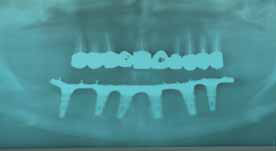

È necessario un controllo radiografico a fine intervento (fig. 8) e una buona chiusura della ferita chirurgica (fig. 9). Si rilascia il periostio in modo da far combaciare i lembi senza che vi sia alcuna trazione. Si posizionano gli abutment in resina acetalica sugli impianti non interessati dalla rigenerazione ossea e mediante della resina in una siringa vengono fissati alla protesi totale provvisoria adeguatamente preparata.

Alla prova denti segue la consegna della protesi finita con la chiusura tramite resina degli ancoraggi adeguatamente protetti per una eventuale riapertura. La radiografia finale è sempre un ausilio per valutare la precisione delle diverse connessioni (fig. 12). È importante inoltre lasciare uno spazio per il passaggio dello scovolino intorno agli abutment, affinché per il paziente vi sia la possibilità di una buona igiene orale fondamentale per la durata dei manufatti protesici (fig. 13)